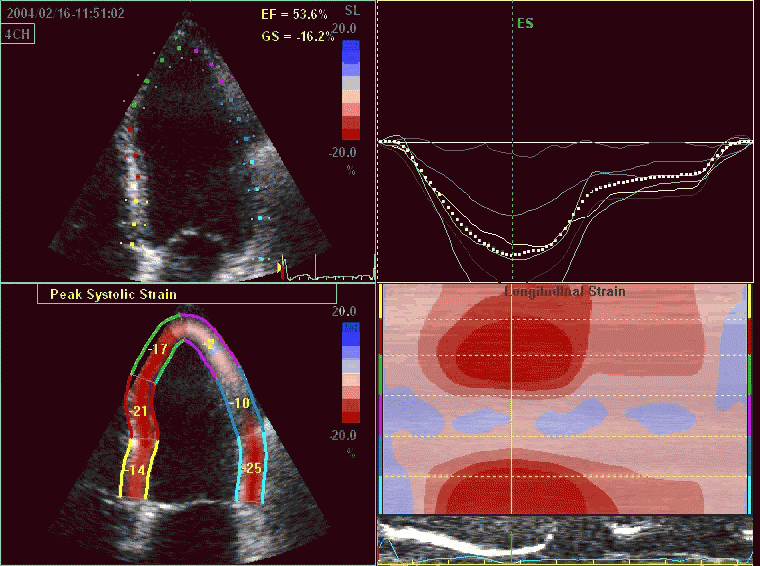

Ecocardiografía con Strain

La ecocardiografía con strain es una variante del ecocardiograma convencional en donde se realiza un análisis de la imagen más avanzado para detectar daño al musculo cardíaco en pacientes que reciben quimioterapia o tiene ciertas formas de insuficiencia cardiaca o inflamación del musculo cardiaco (por virus o enfermedades autoinmunes).

Consiste en la captura y rastreo de puntos del ecocardiograma bidimensional a lo largo del ciclo cardiaco, generando vectores de movimiento y curvas de deformación (strain y strain rate). La deformación medida en planos ortogonales se denomina strain longitudinal, radial y circunferencia.